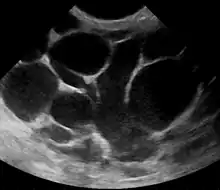

The diagnosis of mastitis and breast abscess can usually be made based on a physical examination.[24] The doctor will also take into account the signs and symptoms of the condition.

However, if the doctor is not sure whether the mass is an abscess or a tumor, a breast ultrasound may be performed. The ultrasound provides a clear image of the breast tissue and may be helpful in distinguishing between simple mastitis and abscess or in diagnosing an abscess deep in the breast. The test consists of placing an ultrasound probe over the breast.

An abscess (or suspected abscess) in the breast may be treated by ultrasound-guided fine-needle aspiration (percutaneous aspiration) or by surgical incision and drainage; each of these approaches is performed under antibiotic coverage. In case of puerperal breast abscess, breastfeeding from the affected breast should be continued where possible.[25][41]

For small breast abscesses, ultrasound-guided fine needle aspiration such as to completely drain the abscess is widely recognized as a preferred initial management.[42]

One recommended treatment includes antibiotics, ultrasound evaluation and, if fluid is present, ultrasound-guided fine needle aspiration of the abscess with an 18 gauge needle, under saline lavage until clear.[43] The exudate is then sent for microbiological analysis for identification of the pathogen and determination of its antibiotic sensitivity profile,[44] which may in turn give an indication for changing the antibiotics. At follow-up, a mammography is performed if the condition has resolved; otherwise the ultrasound-guided fine-needle aspiration with lavage and microbiological analysis is repeated.[45] If three to five aspirations still do not resolve the condition, percutaneous drainage in combination with placement of an indwelling catheter is indicated, and only if several attempts at ultrasound-guided drainage fail, surgical resection of the inflamed lactiferous ducts (preferably performed after the acute episode is over).[46] It is noted, however, that even the excision of the affected ducts does not necessarily prevent recurrence.[46]